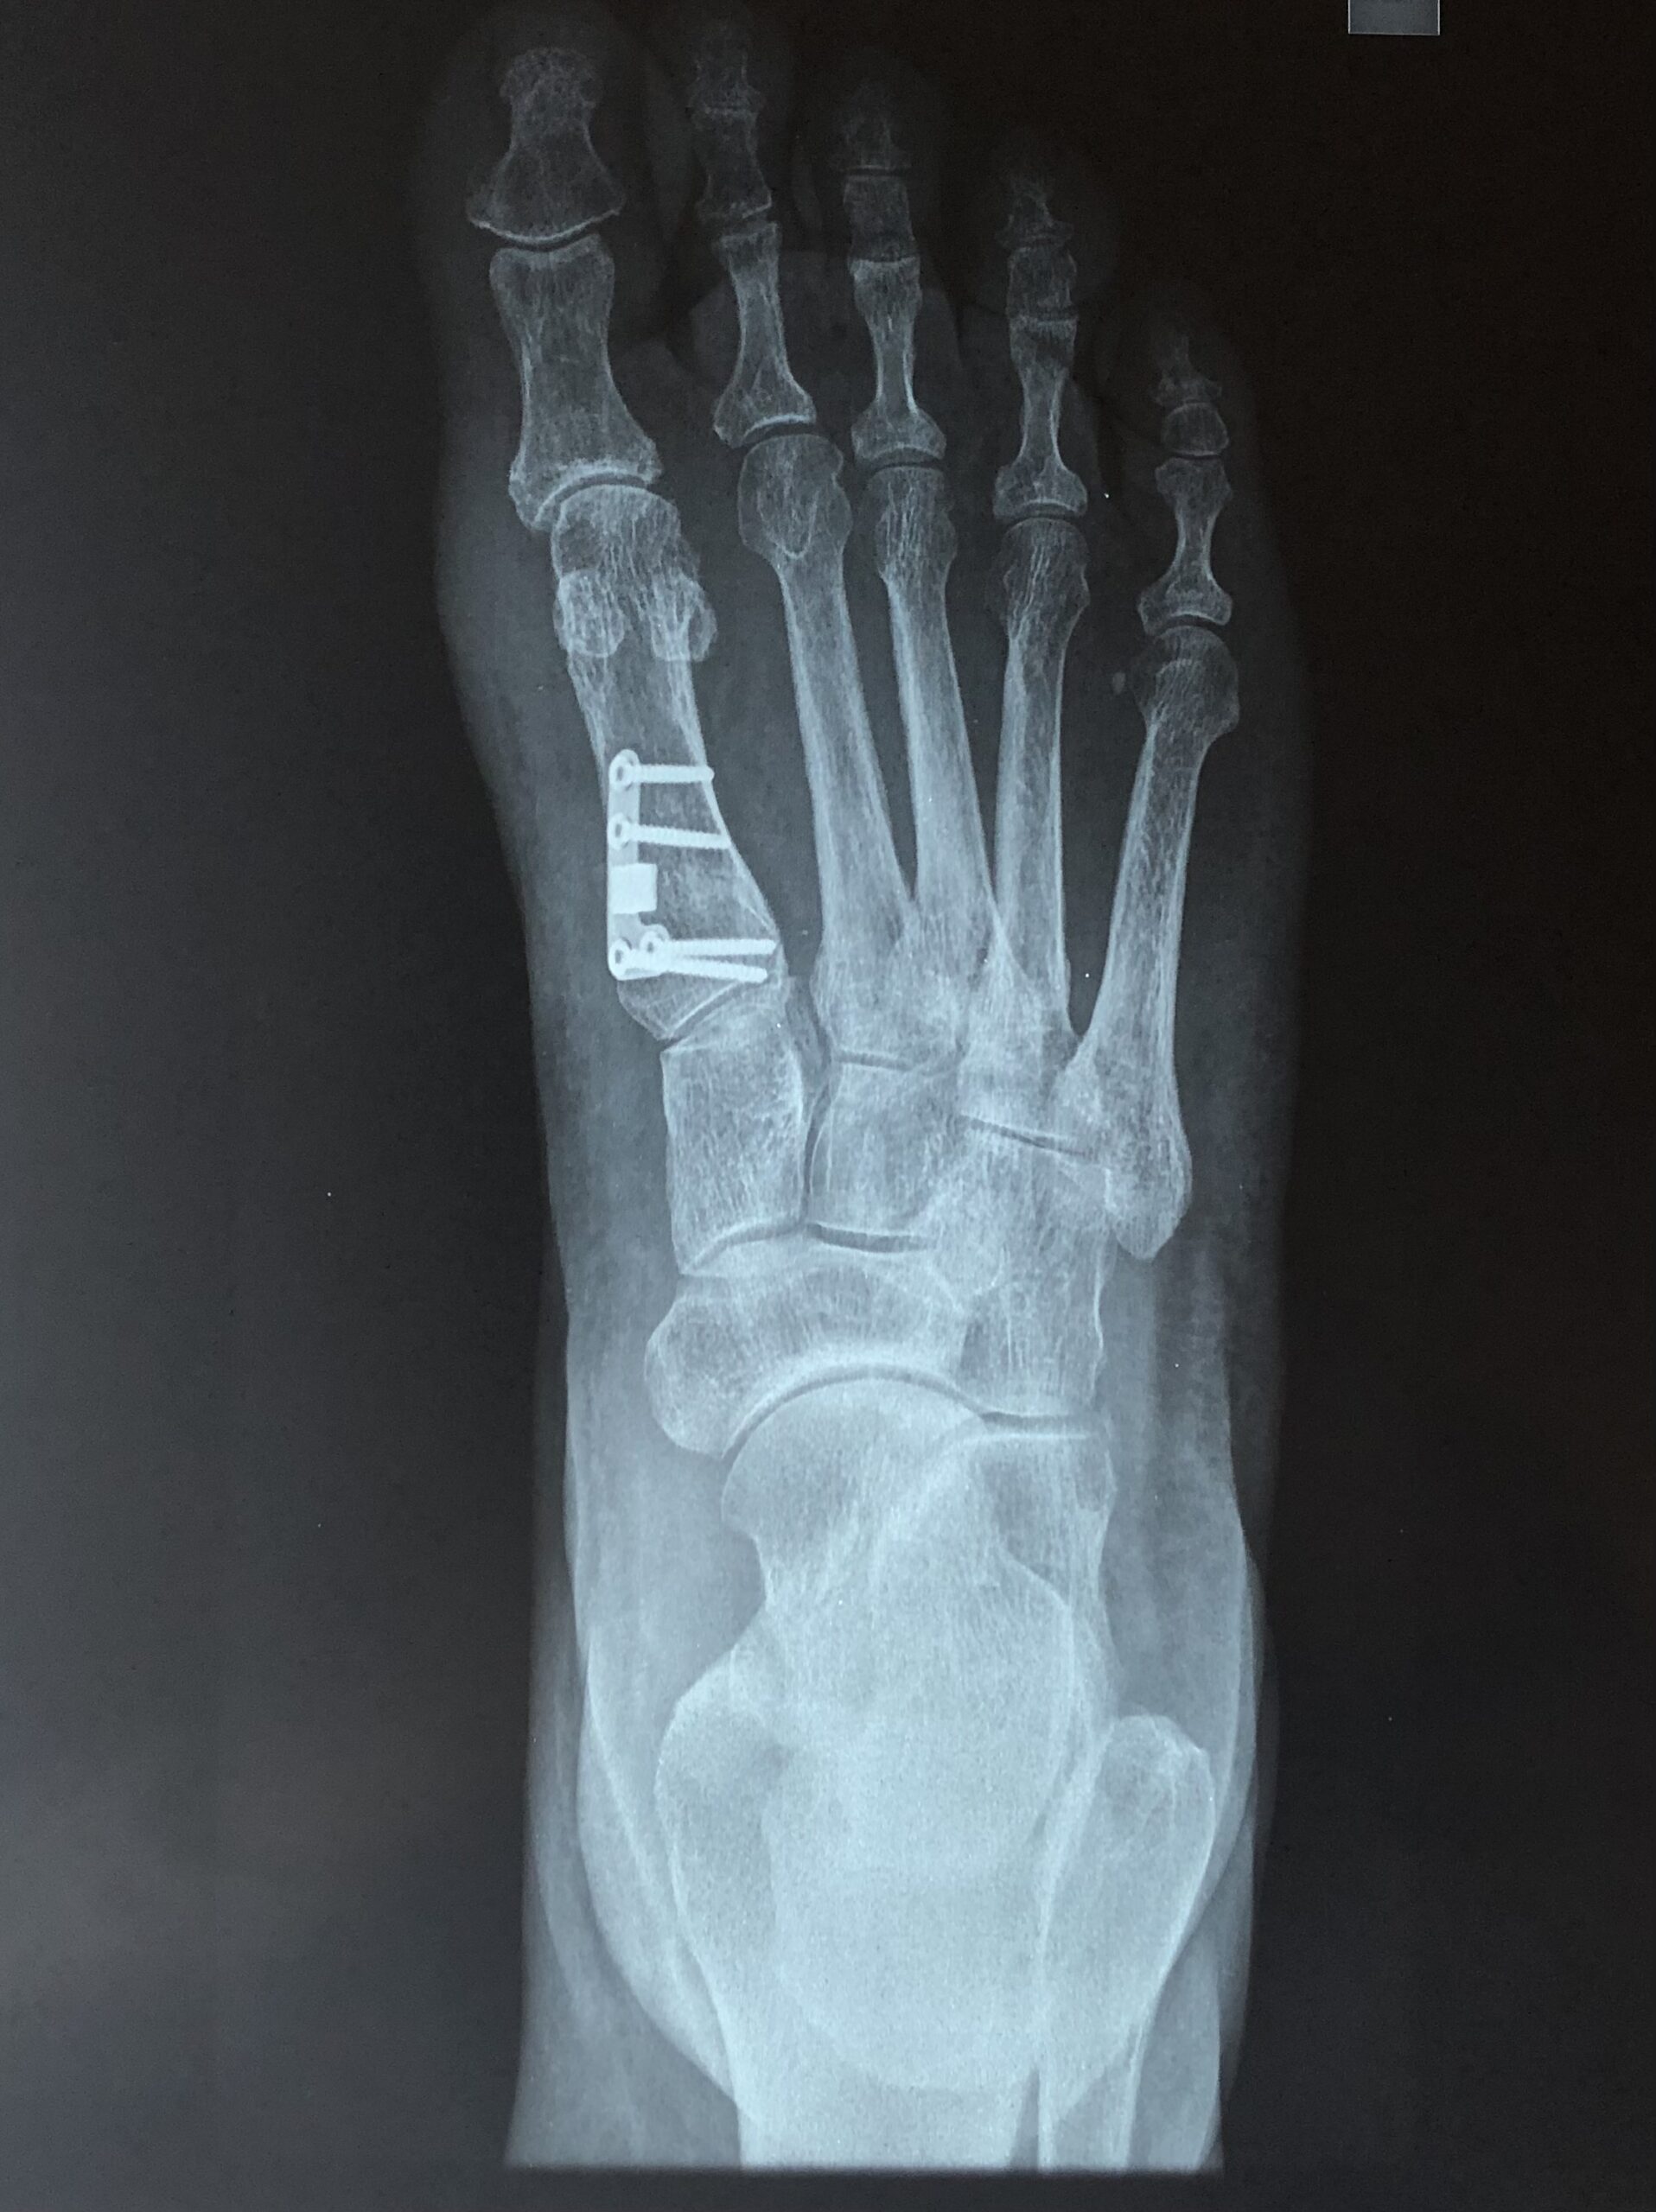

Η διάγνωση της πάθησης πραγματοποιείται εύκολα, καθώς η παραμόρφωση είναι εμφανής ακόμη και στα αρχικά στάδια της πάθησης. Ο θεράπων ορθοπαιδικός προχωρά αρχικά σε μια λεπτομερή λήψη του ατομικού ιστορικού του ασθενούς και στην κλινική εξέτασή του. Παρόλο που η διάγνωση πραγματοποιείται εύκολα μέσω αυτής, ο ακτινολογικός έλεγχος είναι απαραίτητος, για τη σταδιοποίηση της πάθησης (μέτρηση γωνίας βλαισότητας μεγάλου δακτύλου, διαμετατάρσιας γωνίας, γωνίας περιφερικής άρθρωσης μεταταρσίου, κλπ.) Ο καθορισμός του σταδίου είναι βαρύνουσας σημασίας για την επιλογή της κατάλληλης θεραπείας για τον κάθε ασθενή.

Έχουν περιγραφεί στην διεθνή βιβλιογραφία πάνω από 130 διαφορετικές χειρουργικές τεχνικές για την διόρθωση του βλαισού μεγάλου δακτύλου. Περιλαμβάνουν επεμβάσεις στα μαλακά μόρια της άρθρωσης (θύλακος, σύνδεσμοι, τένοντες) και στα οστά με διενέργεια διορθωτικών οστεοτομιών (σε διαφορα επίπεδα του πρώτου μεταταρσίου και της εγγύς φάλαγγας του μεγάλου δακτύλου). Η χρήση της πιο κατάλληλης τεχνικής και ο συνδυασμός αυτών καθορίζεται από τον βαθμό της παραμόρφωσης, από την ακτινολογικά της χαρακτηριστικά, αλλά και από τις δραστηριότητες του ασθενούς.